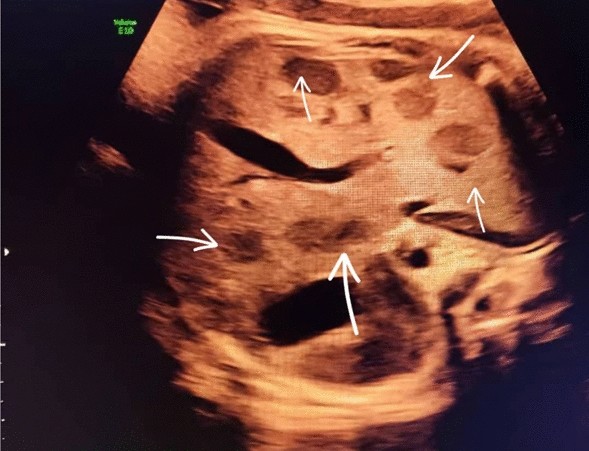

At 37 weeks of gestation, a routine third-trimester ultrasound revealed a hypoechoic lesions in the fetal liver. The lesions were well-circumscribed, measuring approximately 3.5 cm in diameter, and exhibited characteristics suggestive of a vascular tumor. Doppler imaging indicated hypervascularity, raising suspicion for a hemangioendothelioma. Furthermore, the fetal brain appeared normal upon prenatal evaluation. Amniotic fluid levels and fetal growth parameters were within normal limits, and no signs of fetal hydrops were observed. Amniotic fluid levels and fetal growth parameters were within normal limits, and no signs of fetal hydrops were observed. The fetal echocardiogram was normal. Figures 1, 2, and 3

Transverse view of the fetal abdomen obtained by sonography shows multiple hypoechoic lesions, indicated by arrows